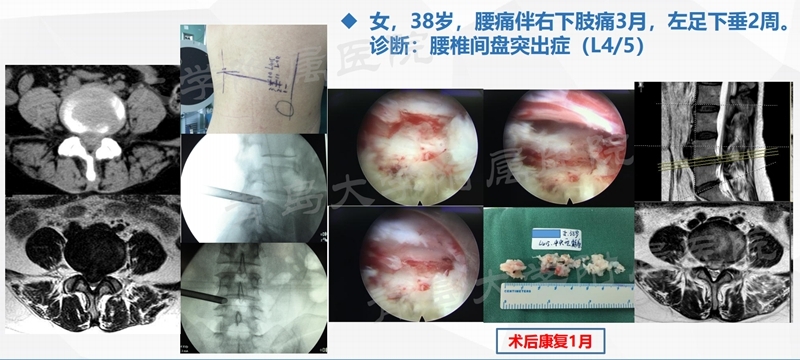

典型案例

案例二